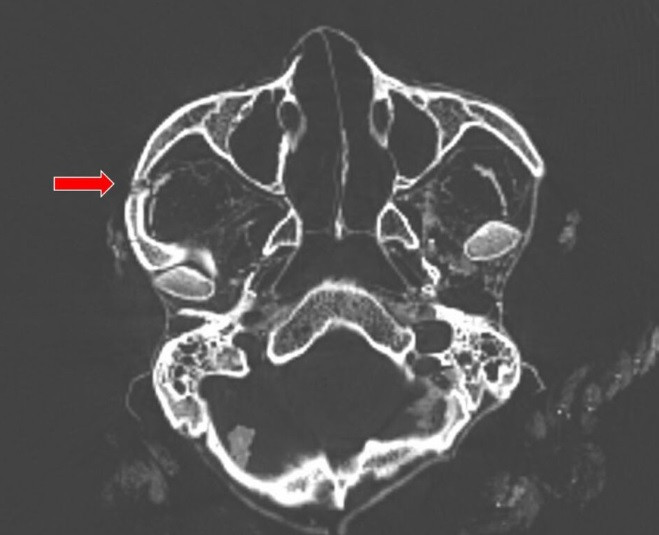

Từ các đặc điểm xương và kết quả phân tích xác ướp bằng phương pháp chụp cắt lớp vi tính 3D (3D-CT), nhóm nghiên cứu ước tính người đàn ông qua đời khi khoảng 20 - 25 tuổi, cao khoảng 1,72m.

Cụ thể, kết quả phân tích bằng 3D-CT chỉ ra người đàn ông trên tử vong do cú đánh chí mạng vào đầu và bị đâm vào lưng trong lúc đang đứng hoặc quỳ. Những vết thương nghiêm trọng này gây ra bởi một hoặc hai kẻ tấn công vào khoảng năm 996 - 1147.